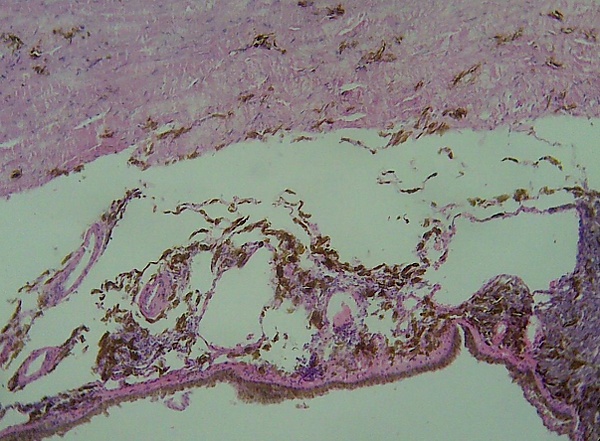

- Лентигинозная меланома слизистых оболочек — 1 % от общего числа меланом. Встречается в полости носа, рта, перианальной и вульвовагинальной областях. Характеризуется выраженной, неравномерной пигментацией.

- Окончательный диагноз меланомы может быть установлен только после гистологического исследования, проведённого после тотального удаления невуса (опухоли) с достаточным захватом здоровых тканей. Предоперационная биопсия с помощью иглы или частичного удаления противопоказана, во избежание распространения меланомы. Определяется глубина прорастания (Clark, Breslow) и митотический индекс.

Клеточный состав меланомы не влияет на клиническое течение опухолевого процесса, однако такие признаки, как митотический индекс, уровень инвазии в дерму, изъязвление и некоторые другие, имеют прогностическое значение. Глубина инвазии меланомы остаётся лучшим прогностическим показателем. На этом основан расчёт пятилетней выживаемости больных с этим новообразованием (англ. Five Year Survival FYS).